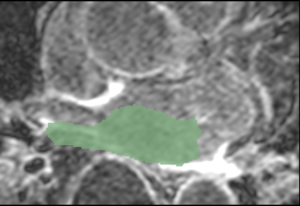

Example 3

CAMRA N26 LGE.png

CARMA N26 Endo.png

Cropped MRI image overlaid with the algorithm-defined blood pool. Expert manual segmentations (white) overlaid with the algorithm-defined blood pool (green).

Note: The last segmentation (red) was derived from an image in the atlas; the other segmentations (green) were derived from similarly-cropped images, not in the atlas.